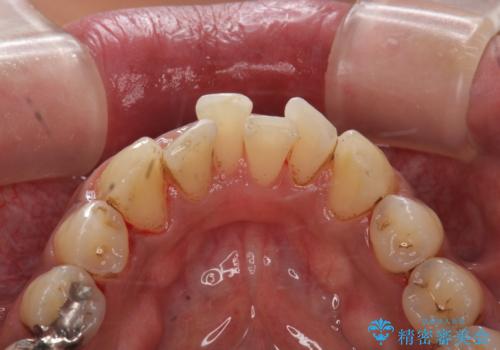

タバコによるヤニ、着色、歯の汚れをPMTC(60分コース)で除去。

- 長年の喫煙による歯の着色をきれいにしたいと、来院されました。

全体にかなり付着していましたので、PMTC(医院で行うプロフェッショナルクリーニング)60分コースを

おすすめしました。

PMTC(60分コース) 担当衛生士 進藤

着色だけでなく歯の表面の汚れもきれいにし、歯の表面がツルツルになって

気持ちがいいと、大変満足していただけました。